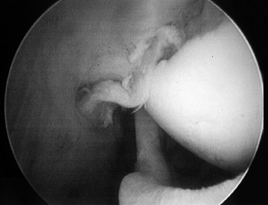

-

and reparability of a tear (Fig. 79.11 and Fig. 79.12). If the tear appears reparable with or without mobilization of the cuff, proceed with arthroscopic repair. (See below for the management of irreparable tears.) After decompression, perform arthroscopic mobilization of the cuff if desired, or proceed with open surgery.

Figure 79.11.

Arthroscopic view of a full-thickness tear with an obvious acromial

spur overhead and an intact biceps tendon beneath a slightly retracted

tear of supraspinatus.